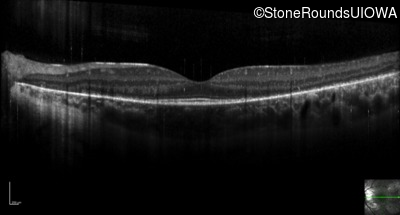

Optical Coherence Tomography - Right - 20/20 -1 sc

Exemplar / OCT Stack

OCT Stack